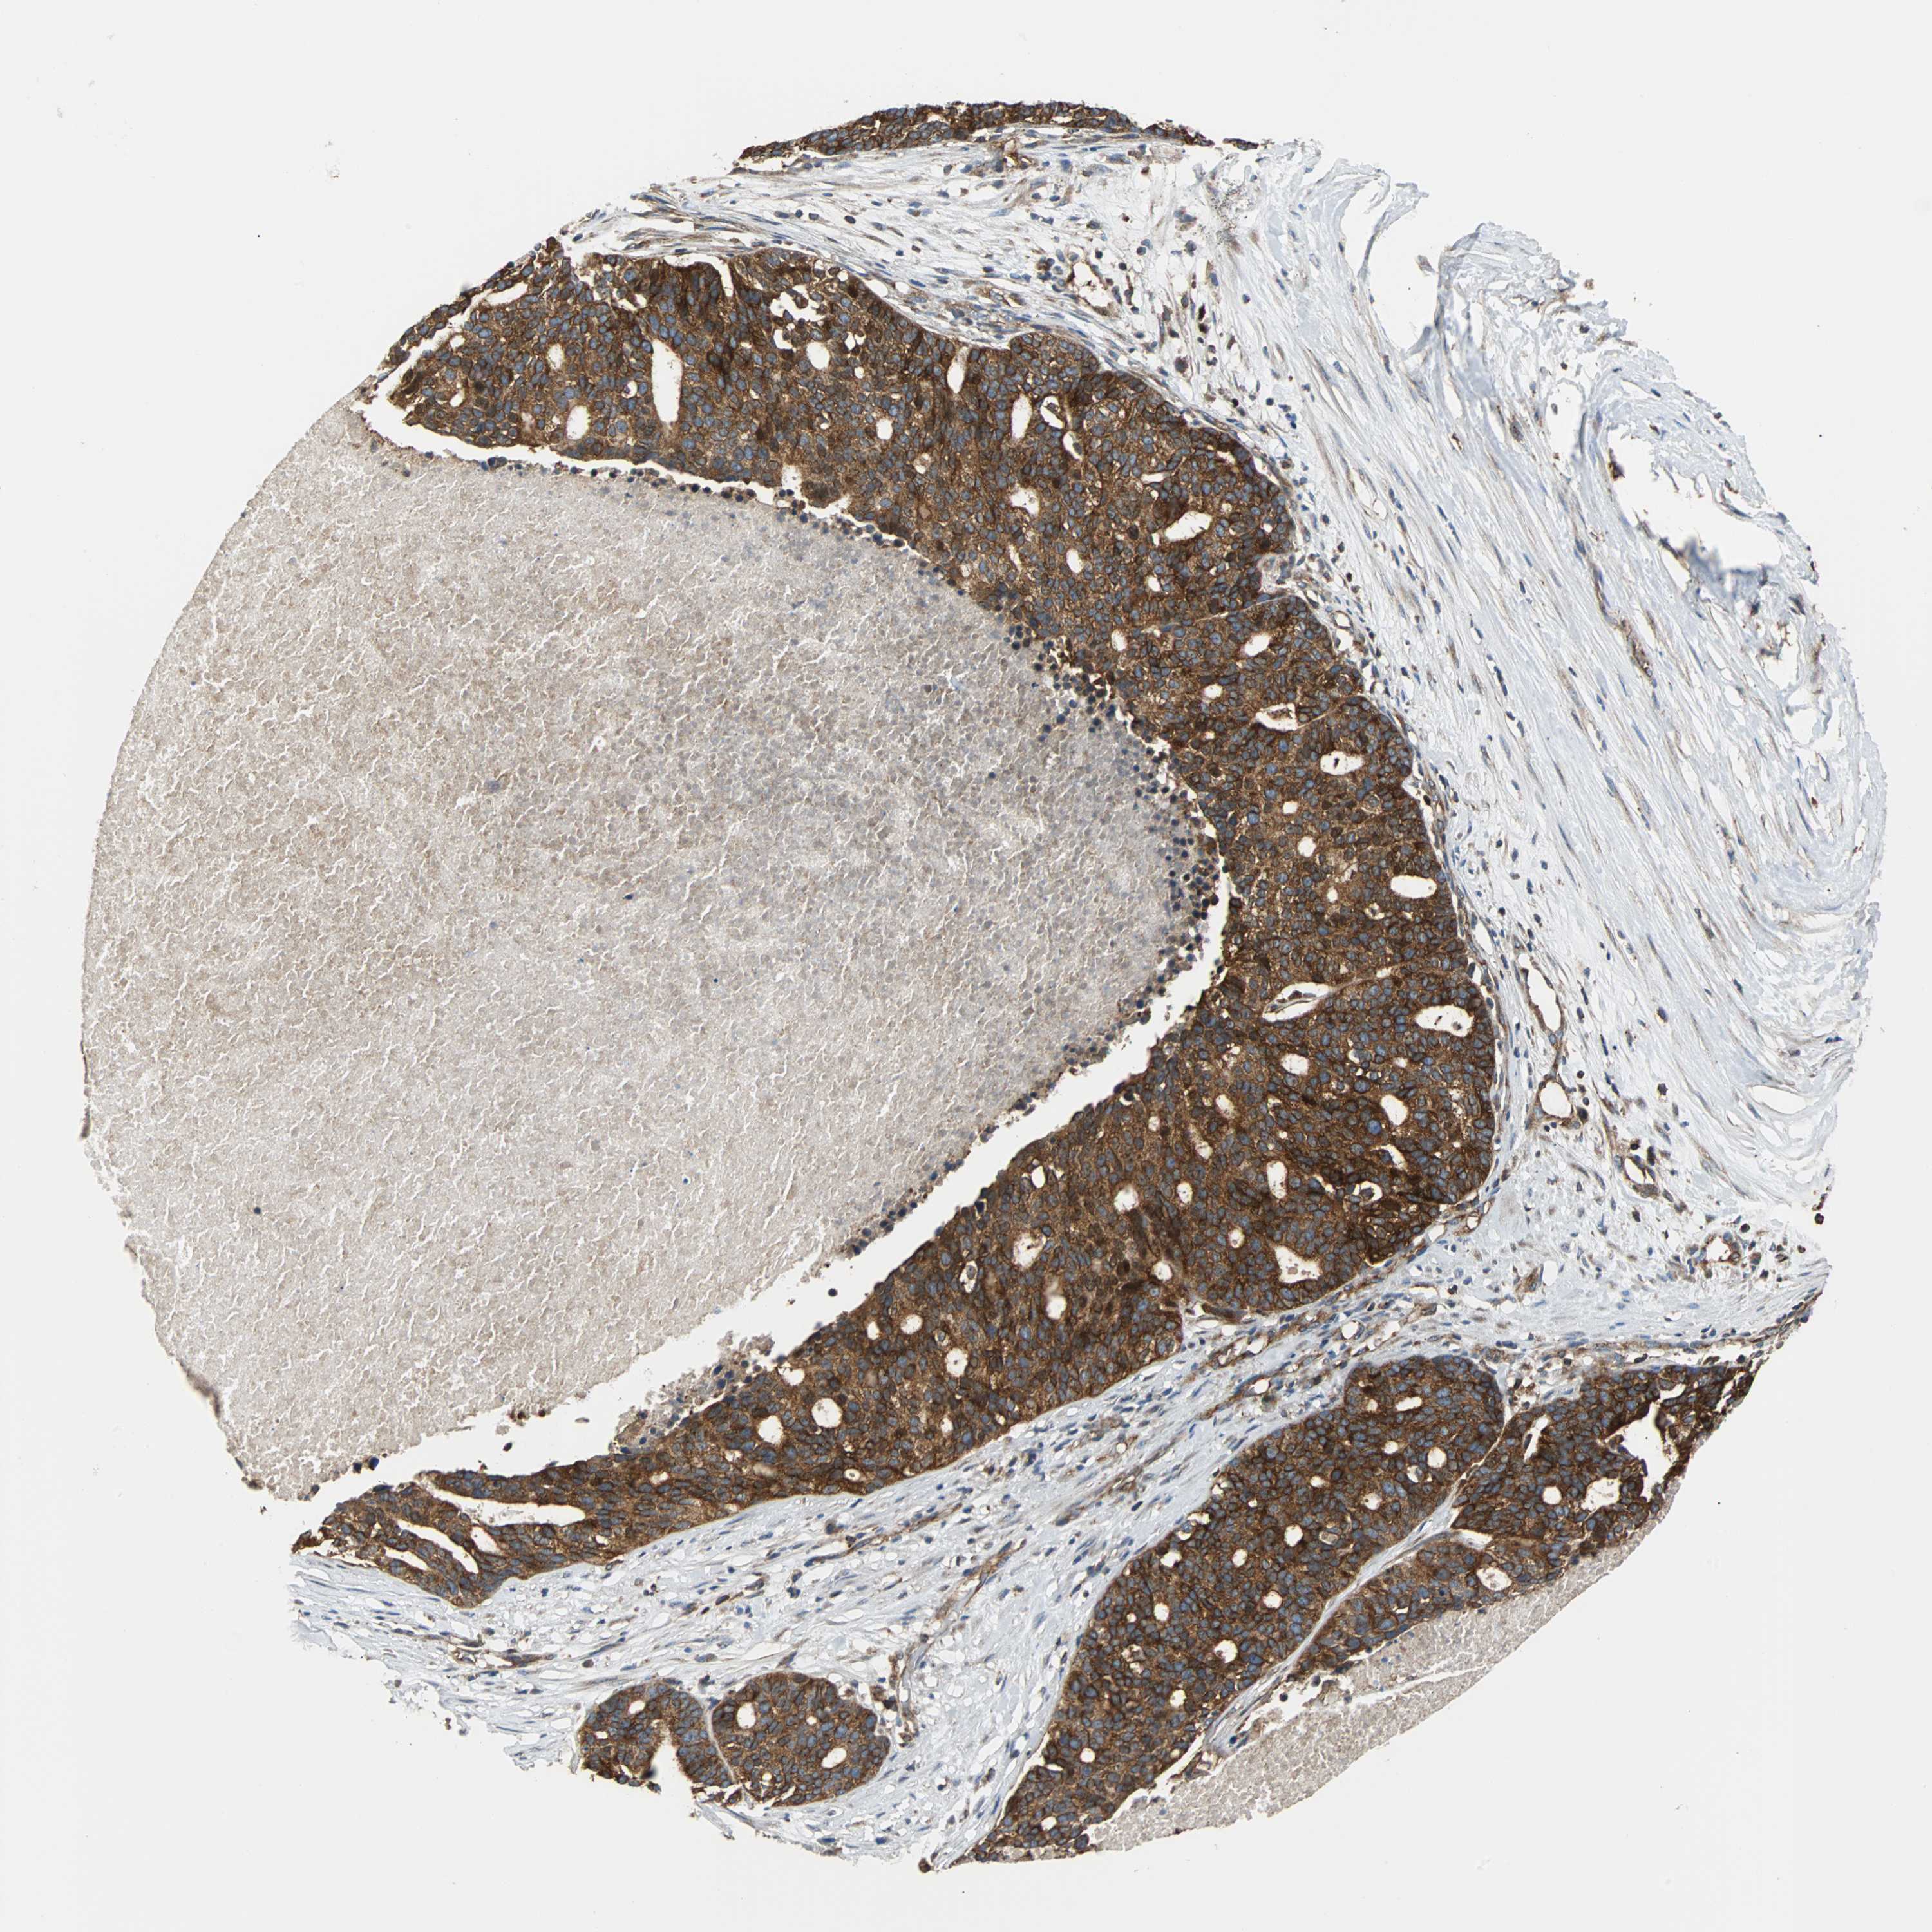

OVARIAN CANCER - Protein expressioni

A mouse-over function shows sample information and annotation data. Click on an image to view it in a full screen mode. Samples can be filtered based on level of antibody staining by selecting one or several of the following categories: high, medium, low and not detected. The assay and annotation is described here.

Note that samples used for immunohistochemistry by the Human Protein Atlas do not correspond to samples in the TCGA dataset.

Antibody stainingi

Antibody staining in the annotated cell types in the current human tissue is reported as not detected, low, medium, or high, based on conventional immunohistochemistry profiling in selected tissues. This score is based on the combination of the staining intensity and fraction of stained cells.

Each image is clickable and will lead to virtual microscopy that enables deeper exploration of all samples and also displays staining intensity scores, fraction scores and subcellular localization as well as patient and tissue information for each sample.

Antibody CAB004264

Antibody CAB005030

Staining

High

Medium

Low

Not detected

Intensity

Strong

Moderate

Weak

Negative

Quantity

>75%

75%-25%

<25%

None

Location

Nuclear

Cytoplasmic/membranous

Cytoplasmic/membranous,nuclear

Cystadenocarcinoma, serous, NOS

Carcinoma, endometroid

Carcinoma, NOS

Cystadenocarcinoma, mucinous, NOS